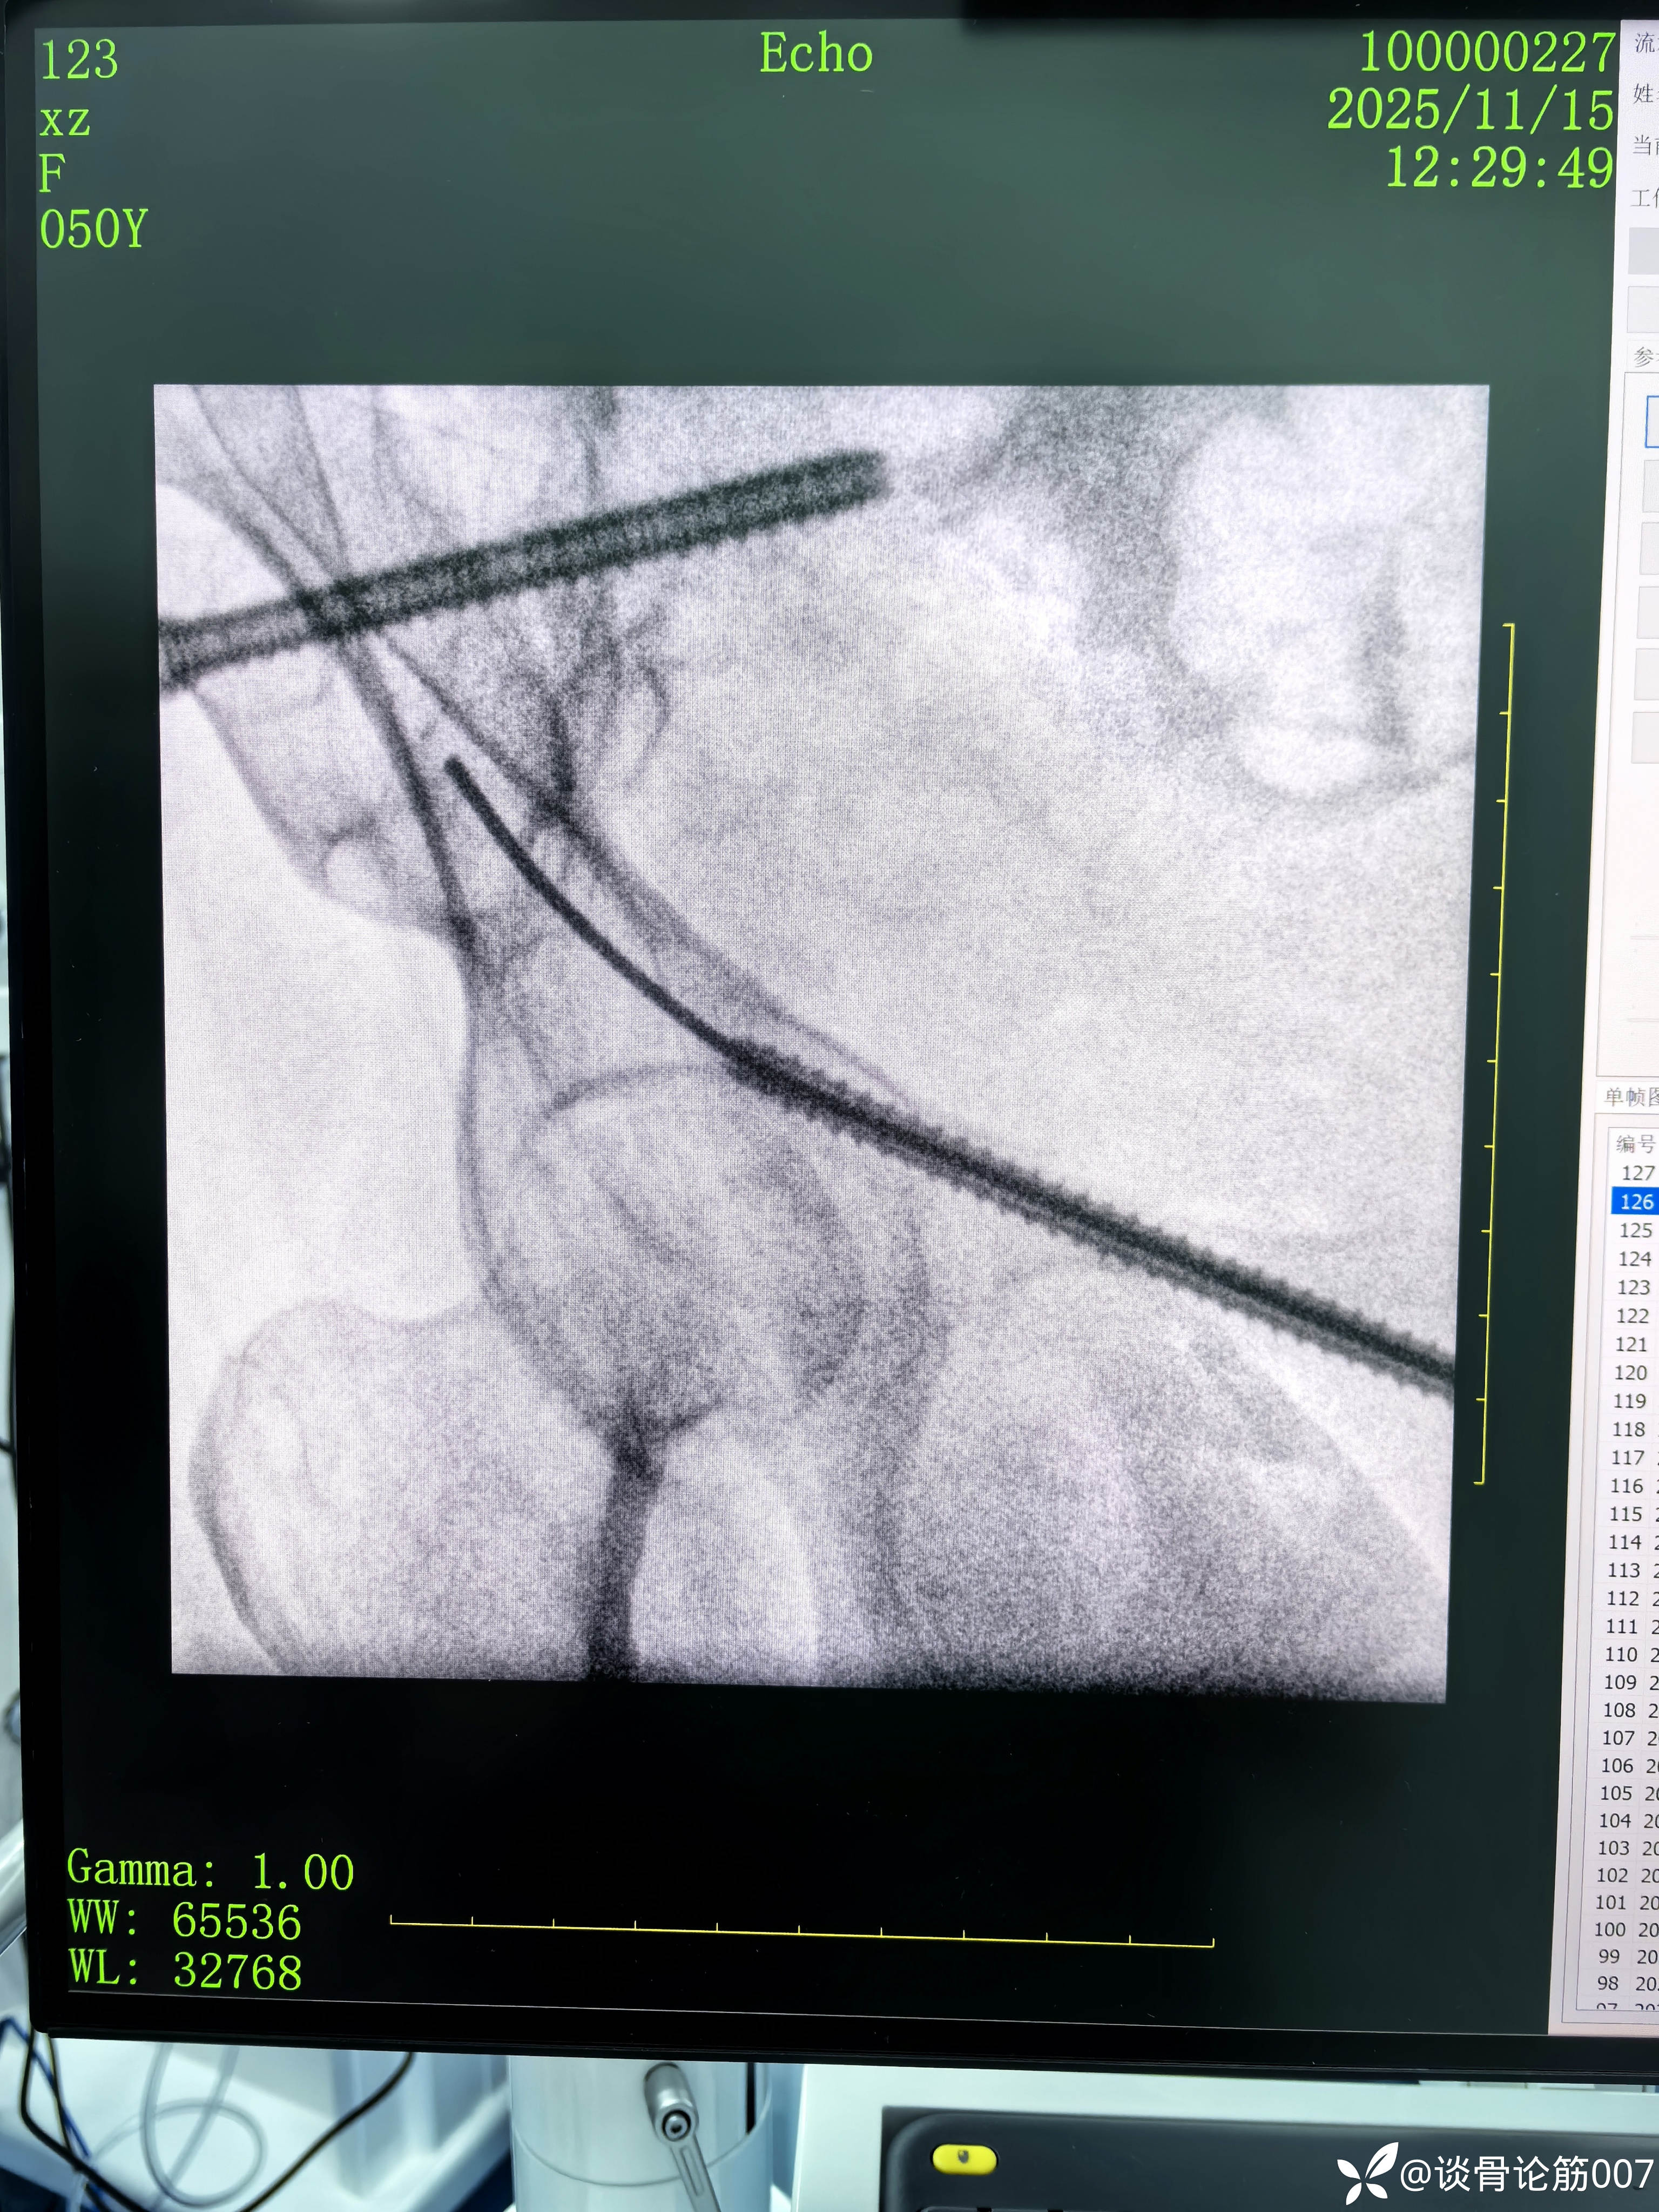

骶髂螺钉+耻骨上支螺钉实操

骨盆B型骨折,给予闭合复位骶髂螺钉+耻骨上支螺钉固定。

髂耻线比较高,骶髂螺钉相对简单一点

应用蛇钉技术避开髋臼

钉道方向还是有点差强人意